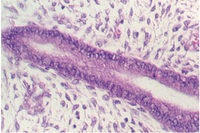

The cervix continues and joins with the vagina. The cervix is lined by simple high columnar epithelium which consists of mucous cells. These are shown in the following views. In the lowest magnification, one can see bundles of smooth muscle in the wall (see below)